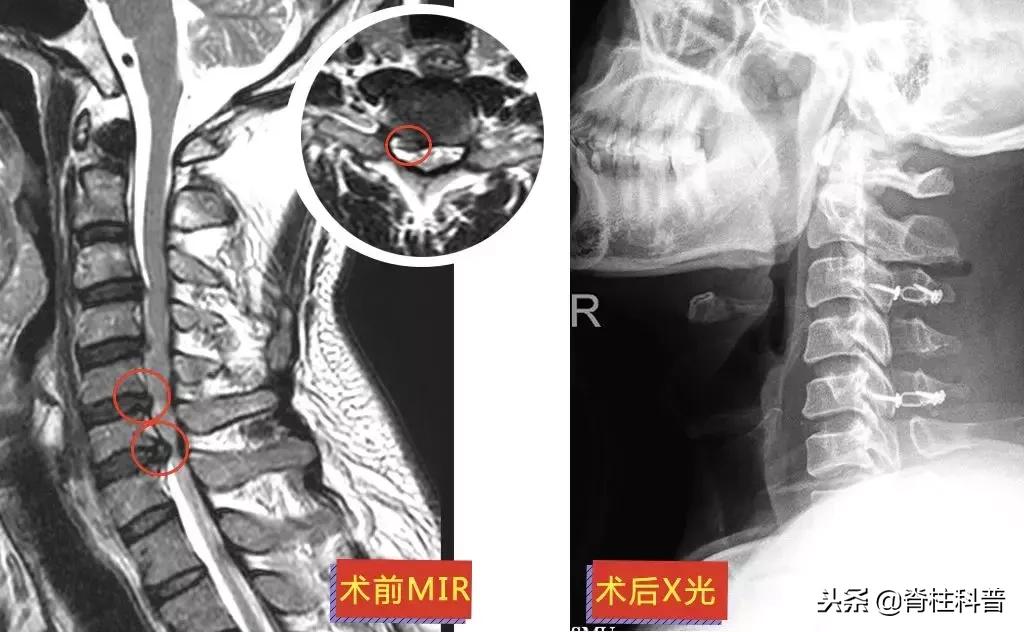

▲ 黄三叔:术前MRI与术后X光

和大部分病人一样,为了避免手术治疗,他们都“竭尽所能”。牵引、针灸、推拿治疗是常见的保守治疗方法,保守治疗的效果如何,需要根据不同的病情来做判断,在此按下不表。下面这位黄三叔经过“脱水治疗”,却是效果欠佳。